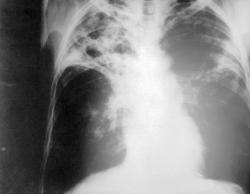

TUBERCULOSIS

Mycobacterium tuberculosis

La tuberculosis primaria es no sensibilizada y es propiamente del pulmón

Los bacilos inhalados se implantan en los espacios aéreos distales de la parte inferior del lóbulo superior o la parte superior del lóbulo inferior

Sensibilización: o foco de Ghon

Radiológicamente se ven las cavitaciones